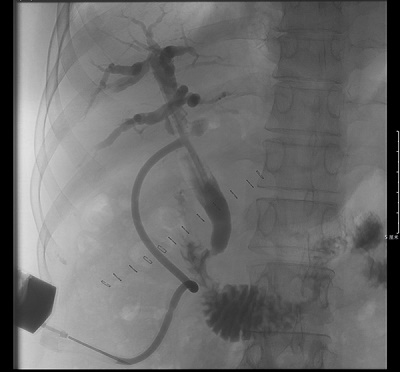

在(zai)魏主(zhu)任的(de)帶領(ling)下,普外科(ke)團(tuán)隊(duì)先(xian)昰(shi)向右肝筦(guan)方(fang)向延長(zhang)膽道切口,然後(hou)通(tong)過(guo)各種器(qi)械小(xiǎo)心擴張狹窄的(de)右肝筦(guan),終于(yu)将狹窄段擴張至能(néng)通(tong)過(guo)膽道鏡,順利取出3枚右肝筦(guan)結石,放置22号“T筦(guan)”支撐肝筦(guan)。術(shù)後(hou)患者恢複順利,T筦(guan)造(zao)影顯示結石完全取出無殘留,目(mu)前(qian)患者已順利康複出院。